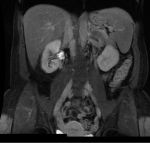

Hi Caryn, What you have posted is a single, coronal , early venous phase T1 weighted scan. You can see the liver, spleen and kidneys. The kidneys look white due to the contrast. Unfortunately, an MR scan produces data that could provide hundreds of images. These are taken in transverse, coronal and sagittal planes. They are also done in T1, T2 and Spinecho sequences. They are also done in noncontrast, arterial, saturation, venous and late venous phases. That is why an MR takes a while, and you would have had to 'hold your breath' for each sequence. MR scans are diagnosed on a computer with several high def. screens. Images are manipulated, 3D images are obtained, and by scrolling through the images of all of the sequences, a diagnosis is made. Sample images are often printed out for the benefit of the referring doctor.  We used to give patients a CD with relevant films.

Alright, I hope this is a good shot.  From the last test which was a fibroscan, I was told probably between stage 2-3 fibrosis. This is an MRI I had done today in preperation of upcoming treatment.  I hope someone can comment. I wont hold you to it - I am going to see my specialist in a few weeks.